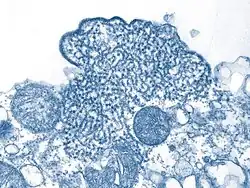

El diagnóstico por laboratorio de esta enfermedad puede realizarse de forma precoz con la técnica PCR, al aislar el virus de muestras tomadas de la garganta, hisopado nasal, líquido cefalorraquídeo, orina y sangre. Los anticuerpos IgG e IgM pueden detectarse de forma más tardía que el material genético viral, la detección de estos anticuerpos suele realizarse con la técnica ELISA. El virus también puede ser aislado con inmunohistoquímica en análisis de autopsia.[5]